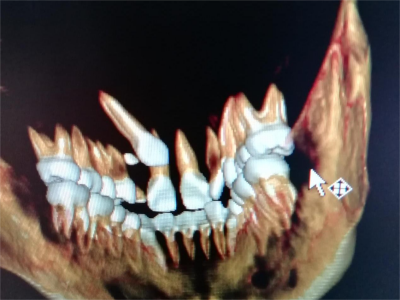

阻生牙主要原因是随着人类的进化,颌骨的退化与牙量的退化不一致,导致骨量相对小于牙量,颌骨缺乏足够的空间容纳全部恒牙。

对于阻生牙的处置需要首先明确阻生牙齿发育情况是否正常,对于由于早期外伤或其他原因造成发育异常,如牙根弯曲、短根等情况的阻生牙,还应根据患者的综合情况,决定牙齿是否保留。

发育正常的牙齿同时正畸治疗又不需要进行拔牙矫治,通常需要对阻生牙进行牵引治疗,引导进入牙弓,而对于发育异常的阻生牙加之正畸治疗需要进行拔牙矫治,通常可以考虑将阻生牙拔除,而避免再拔发育正常的前磨牙,即降低了正畸治疗的难度及不确定性,又保留了相对正常的牙齿。